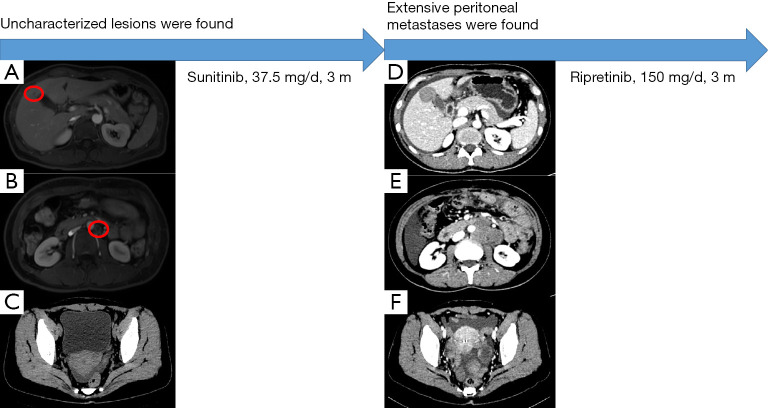

圖1:案例先進階段的圖形摘要。 (A) 該患者的腸套疊 CT。 (B) 在先進次操作中取出的標(biāo)本。 (C) 患者先進次術(shù)后反復(fù)的 CT 圖像。 (D) 在第二次操作中取出的標(biāo)本。 CT,計算機斷層掃描。

術(shù)中發(fā)現(xiàn)小腸近端和中段有一腫瘤,大小約4cm×3cm×2cm,質(zhì)地堅韌(見圖1B)。 未見其他異常體征,如腹水或腹膜內(nèi)轉(zhuǎn)移。 接下來,對小腸和周圍小腸的腫瘤進行了切除。

2020年11月,患者出現(xiàn)左下腹隱痛癥狀。 2020年11月腹部CT示盆腔內(nèi)有少量積液,左上腹腔臍部有一團軟組織影(大小約43mm×43mm×39mm), 它與在小腸手術(shù)中觀察到的上述吻合相鄰(參見圖 1C)。 考慮GIST反復(fù)的可能,不排除GIST轉(zhuǎn)移。 行正電子發(fā)射斷層掃描/CT檢查,結(jié)果顯示GIST術(shù)后,吻合口無明確反復(fù)征象,左腹部鄰近有一個代謝亢進的軟組織腫塊。 因此,考慮淋巴結(jié)轉(zhuǎn)移的可能性。 患者就診于佳學(xué)基因合作醫(yī)院,診斷如下:(一)GIST術(shù)后反復(fù); (二)術(shù)后闌尾炎; (III) 術(shù)后剖宮產(chǎn)。

查體結(jié)果如下:左上腹觸脹; 沒有其他積極跡象。 2020年12月,患者在全身麻醉下接受了剖腹探查術(shù)。 術(shù)中在原空腸-空腸吻合口下方小腸系膜發(fā)現(xiàn)一大小約8cm×7cm×6cm的腫瘤(見圖1D)。 切除了小腸系膜腫瘤和部分小腸。 患者術(shù)后恢復(fù)順利。